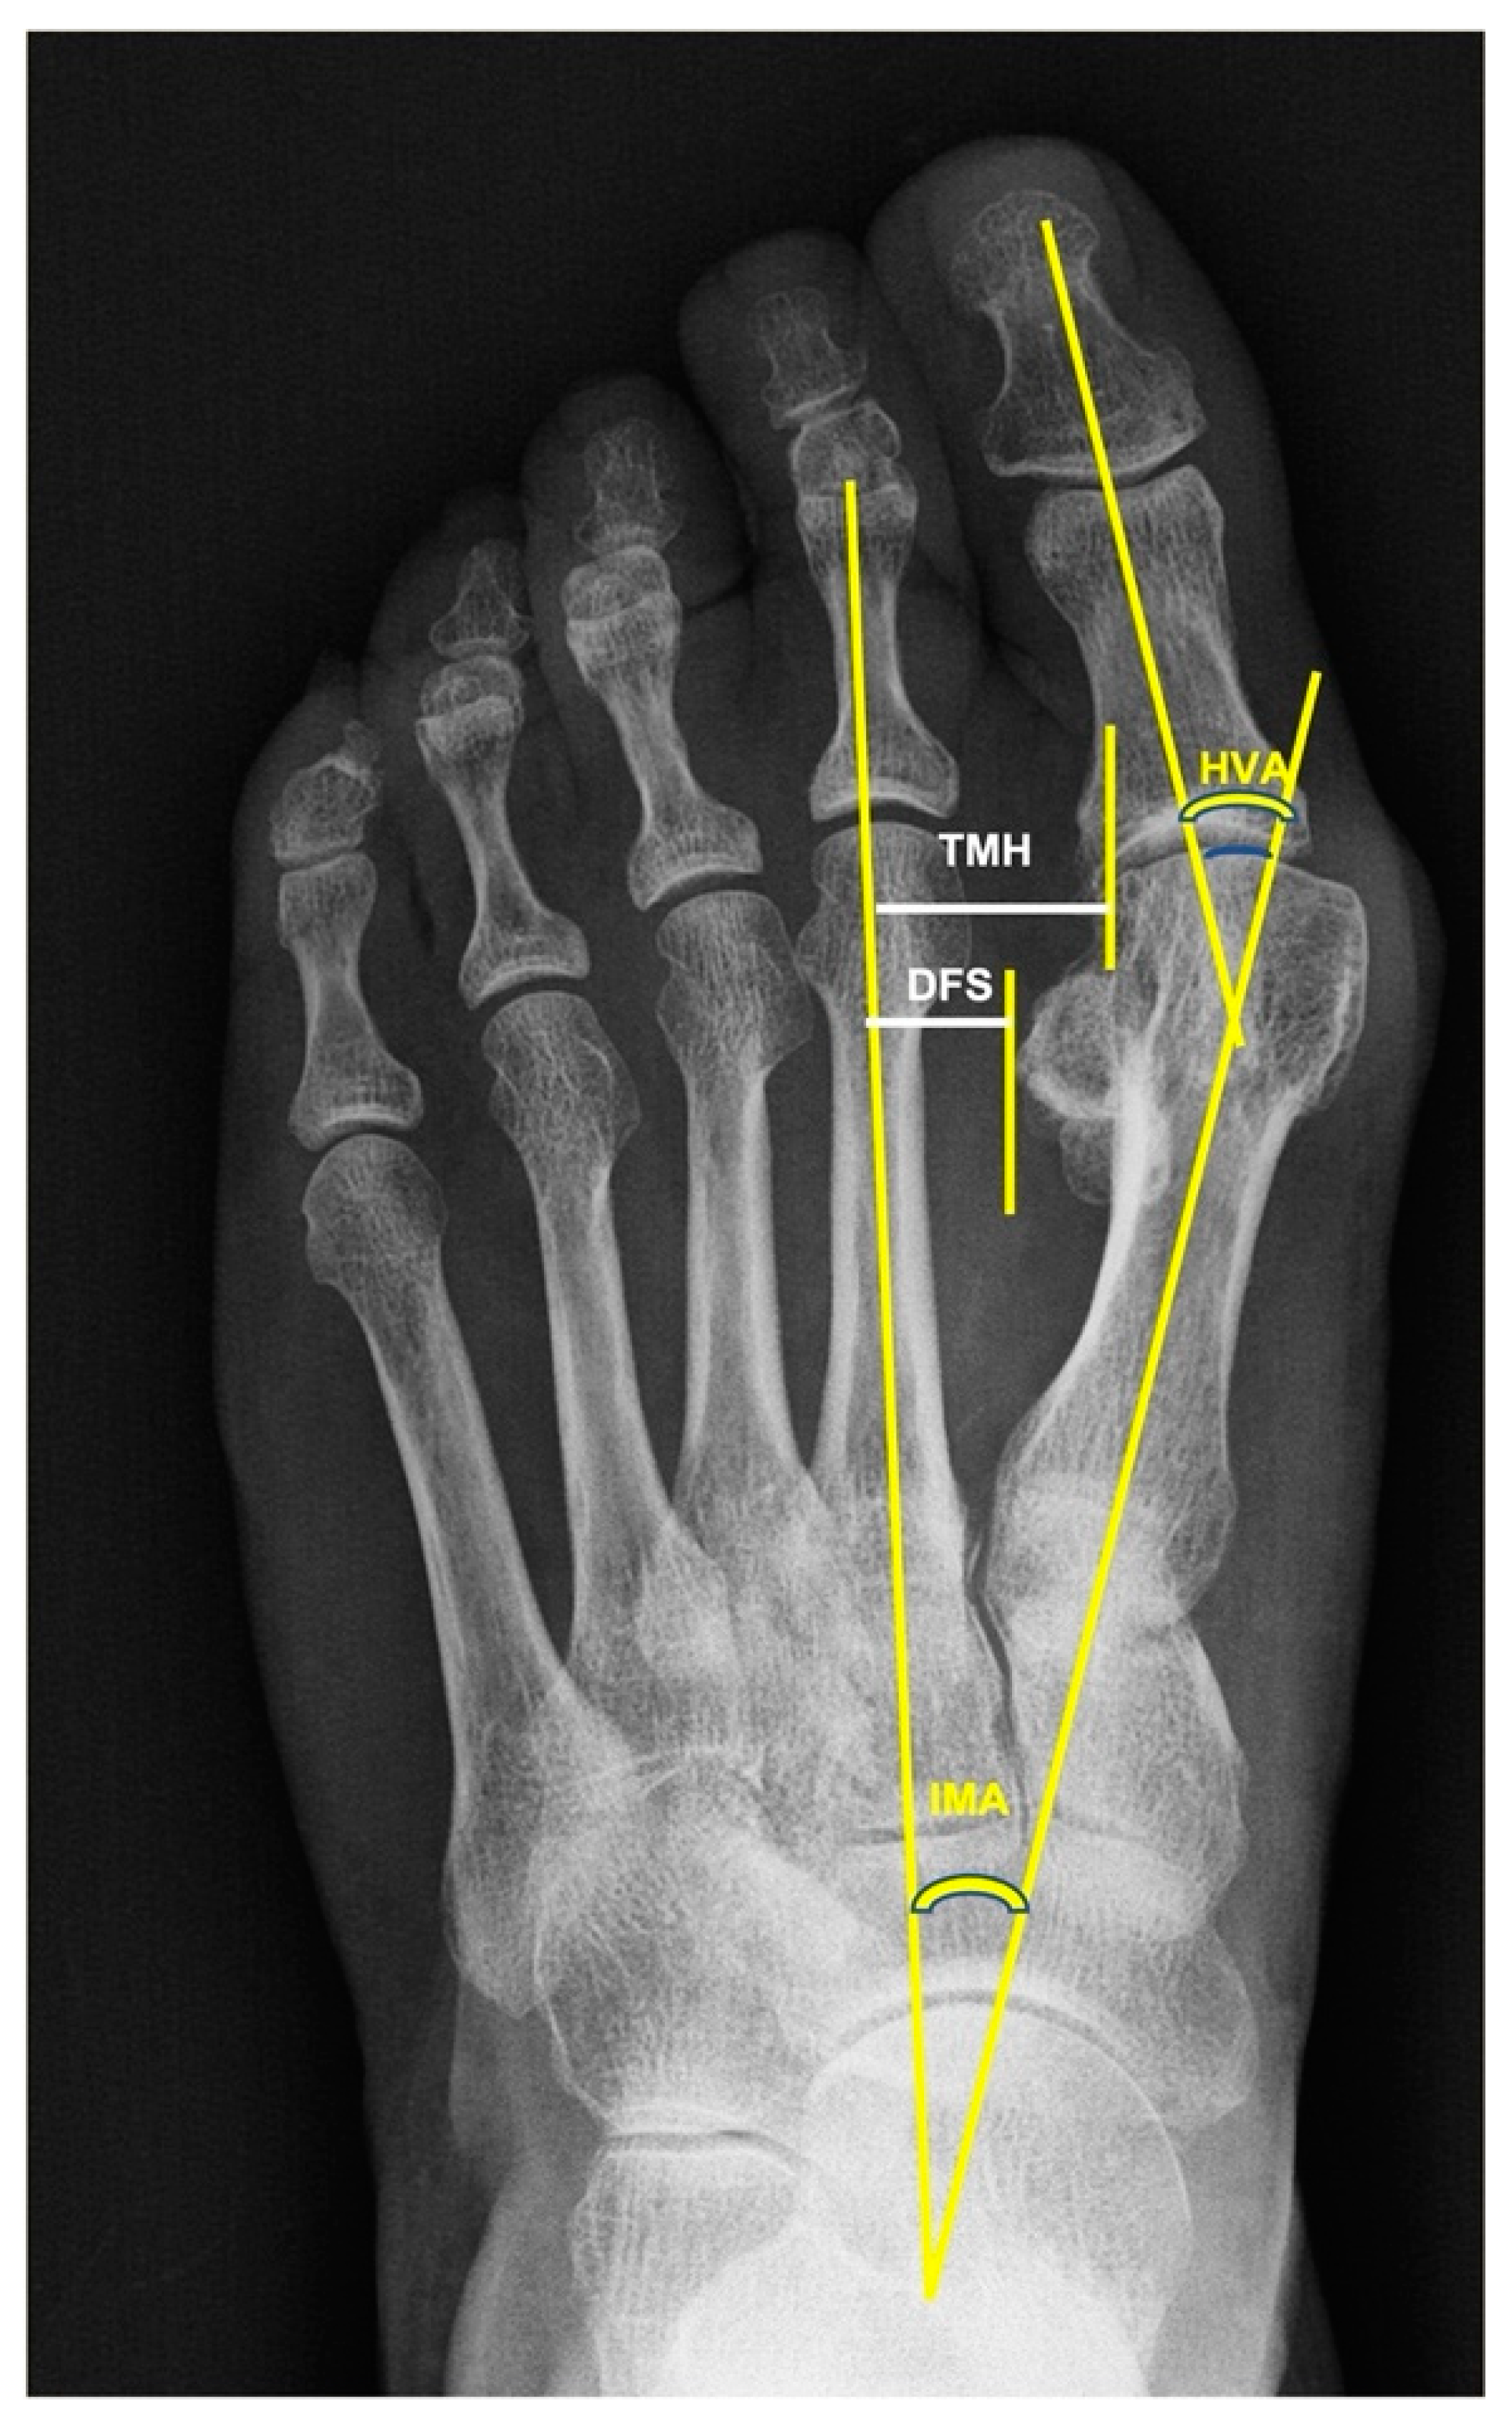

Bunion X Ray Radiology . Abnormal 1st metatarsophalangeal angle and 1st intermetatarsal angle consistent with. Interreader reliability and intermethod performance. bunions are a common foot complaint, and patients may present to their gps seeking advice or referral to an orthopaedic surgeon. heineman n, chhabra a, zhang l, et al. bunionette deformities, commonly called tailor's bunion, are prominences on the lateral aspect of the. The aim of this article is to. hallux valgus, commonly referred to as a bunion, is a complex valgus deformity of the first ray that can cause. Traditional method evaluation of hallux valgus: a bunionette, also known as a tailor's bunion, metatarsus quintus valgus, or digitus quintus varus, is a bony prominence at the lateral 5 th. Check the alignment of your toes and look for damage to the mtp joint. bunion, which is also known as the hallux valgus, refers to a constellation of symptoms including soft tissue swelling over the first.

The postoperative followup Xray shows the measurements of hallux Bunion X Ray Radiology bunion, which is also known as the hallux valgus, refers to a constellation of symptoms including soft tissue swelling over the first. heineman n, chhabra a, zhang l, et al. Traditional method evaluation of hallux valgus: hallux valgus, commonly referred to as a bunion, is a complex valgus deformity of the first ray that can cause. The. Bunion X Ray Radiology.